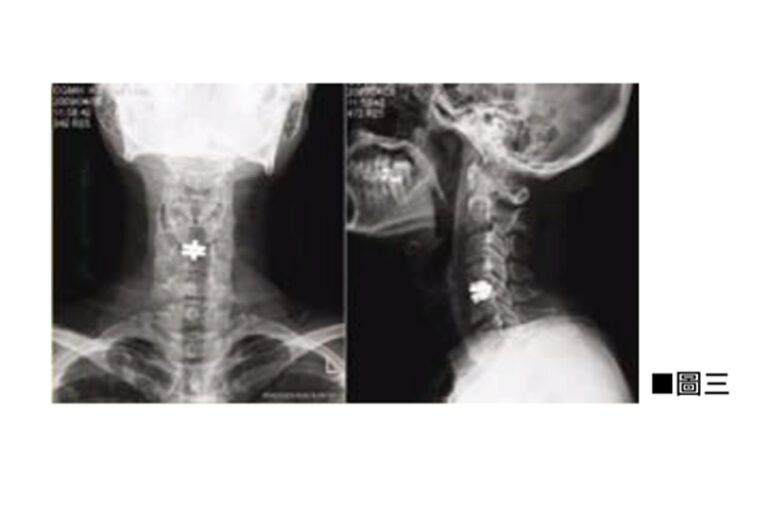

頸椎前路椎間盤切除及椎體融合手術(Anterior Cervical Discectomy and Fusion,ACDF)是以外科手術來治療頸椎的病變問題。導致頸椎病變多是因退化性、勞損性或意外受傷造成。病變會發生在頸椎間盤、頸椎的小面關節,或是頸椎體骨。由於頸椎中央包含了負責控制我們四肢、軀幹及大小便的中樞神經,所以頸椎病人除了有頸椎不穩定的症狀外,亦會有神經受壓的病徵。頸椎不穩定會引起肌肉繃緊、頸背痛、膊頭痛及頭痛。而神經受壓會令感官神經及運動神經功能失調,病人會有手腳神經麻木痺痛、肌肉無力、平衡失調、行路不穩、小便頻密、夜尿及便秘情況。此外反射神經及交感迷走神經的功能失調,亦會導致病人頭暈、耳鳴、腸胃不適甚至情緒不穩定。